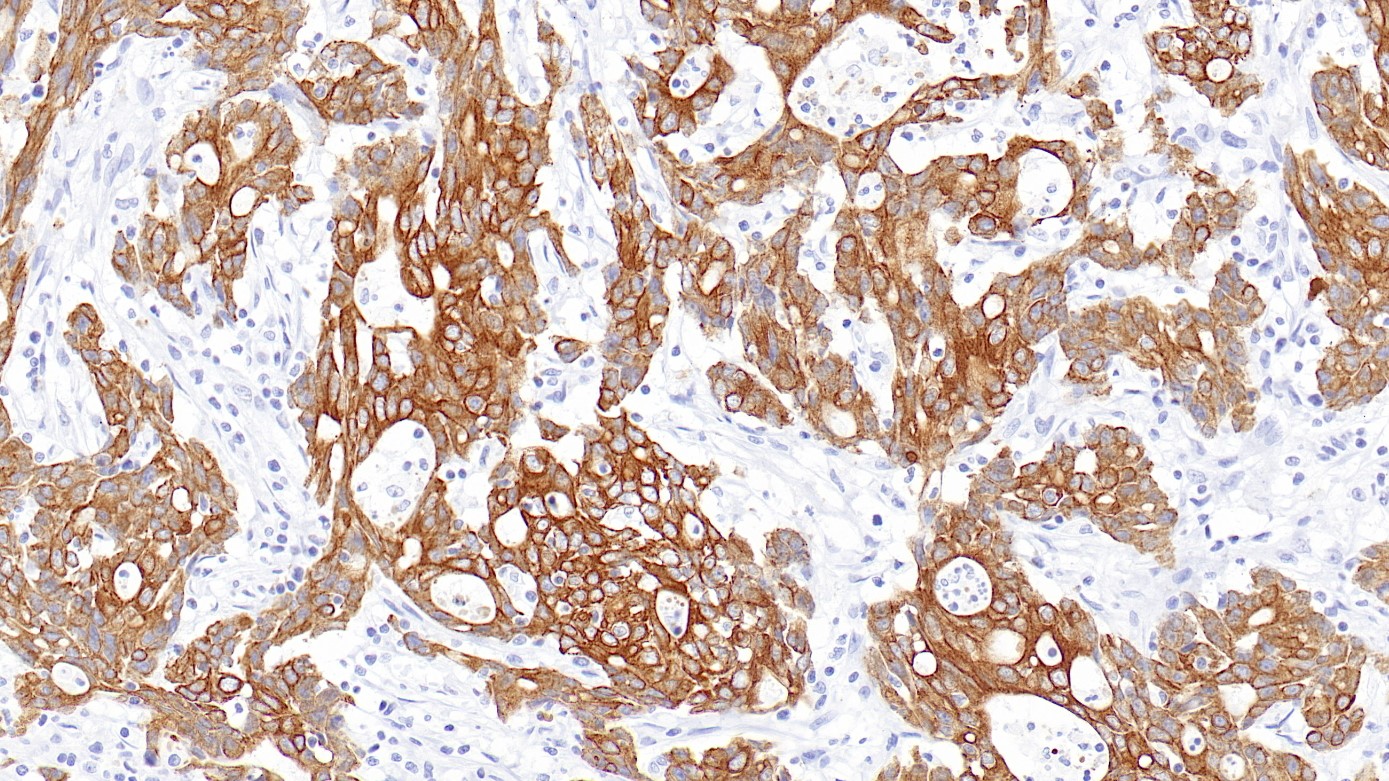

2.High expression of cytokeratin CAM5.2 in esophageal squamous cell carcinoma is associated with poor prognosis.[J]. He Shujin,Peng Jie,Li Lei,Xu Ying,Wu Xiaoxiao,Yu Juan,Liu Jianli,Zhang Jinguo,Zhang Renya,Wang Wei. Medicine. 2019(37)